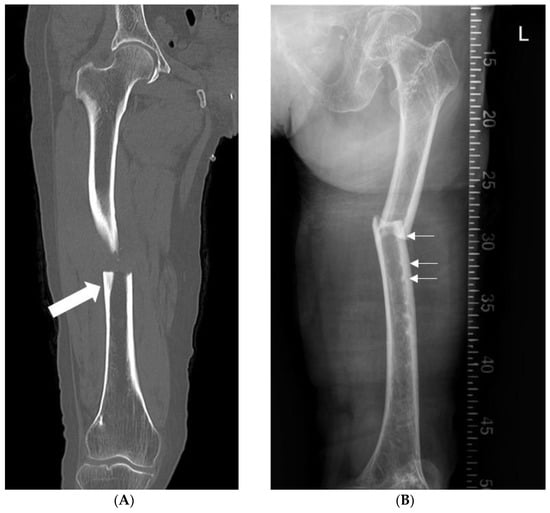

| AFF c location | 0.803 | ||

| Proximal third, n | 6 (30.0%) | 18 (24.0%) | |

| Middle third, n | 13 (65.0%) | 51 (68.0%) | |

| Distal third, n | 1 (5.0%) | 6 (8.0%) | |